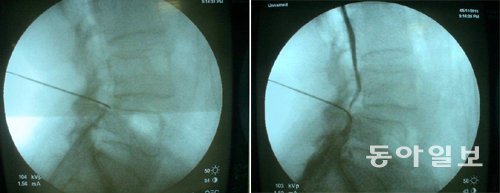

척추협착증 환자들은 FIMS 시술을 통해 척추고혈압 증상을 극복할 수 있다. 왼쪽 사진은 척추관 흐름이 막혀 척추 신경 주위에 조영제가 제대로 흐르지 못하는 모습. 오른쪽 사진은 FIMS 시술을 받은 뒤 조영제 흐름이 원활해진 모습. 안강병원 제공

좁아진 부위를 넓히는 것보다 신경 기능을 회복하는 것이 피와 뇌척수액의 순환을 돕는 데 효과적이다. 특히 ‘FIMS’로 불리는 특수 바늘을 이용한 자극 치료는 신경이나 혈관을 손상시키지 않고 안전하게 치료할 수 있다. FIMS는 배부신경근절에 생긴 병을 손상 없이 치료하는 데 효과적인 치료법으로 손꼽힌다.

FIMS를 통해 척추협착증을 치료하면 신경의 움직임이 좋아져 혈류가 증가한다. 뇌척수액 흐름도 좋아져 척추관 내 압력을 낮출 수 있다. 시술 뒤엔 반드시 운동을 통해 신경이 자기 기능을 유지하고 순환이 잘되도록 노력해야 한다.